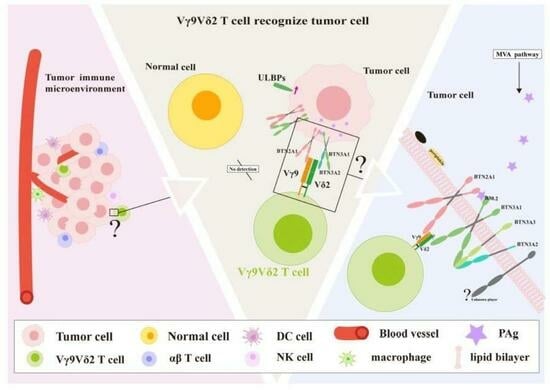

Mechanisms and Functions of γδ T Cells in Tumor Cell Recognition

by

Jing Tang, Chen Wu, Jintong Na, Yamin Deng, Simin Qin, Liping Zhong and Yongxiang Zhao

Curr. Oncol. 2025, 32(6), 329; https://doi.org/10.3390/curroncol32060329 - 3 Jun 2025

γδ T cells are among the first line of defense in the immune system, playing a crucial role in bridging innate and adaptive immunity. Although γδ T cells are crucial for tumor immune surveillance, the complete mechanism by which γδ T cell receptors

γδ T cells are among the first line of defense in the immune system, playing a crucial role in bridging innate and adaptive immunity. Although γδ T cells are crucial for tumor immune surveillance, the complete mechanism by which γδ T cell receptors identify molecular targets in target cells remains unknown. Target cells can produce phosphoantigens (PAgs) via the mevalonate pathway or the methylerythritol phosphate pathway. The BTN3A1–BTN2A1 complex undergoes conformational changes in its extracellular domains upon binding to PAgs, leading to Vγ9Vδ2 T cell recognition. However, the structural basis of how Vγ9Vδ2 T cells recognize changes in this complex remains elusive. This review provides a detailed overview of the historical progress and recent discoveries regarding how Vγ9Vδ2 T cells recognize and target tumor cells. We also discuss the potential of γδ T cells immunotherapy and their role as antitumor agents.

(This article belongs to the Section Cell Therapy)

Graphical abstract